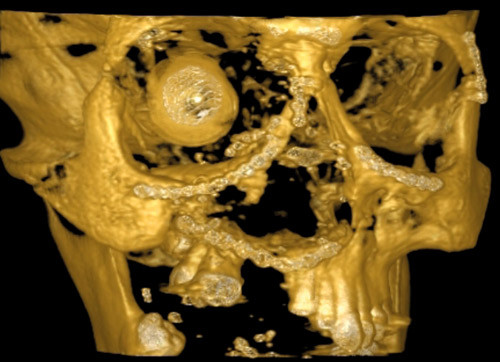

Figur 1 viser avbildning med digital volumtomografi av en pasient med skuddskader etter innsetting av en stor mengde osteosyntesemateriale. Denne metoden ga en fremstilling uten artefakter, mens tradisjonell CT hadde begrenset nytteverdi pga. metallartefakter og utilfredsstillende 3D-modellering (fig 2).